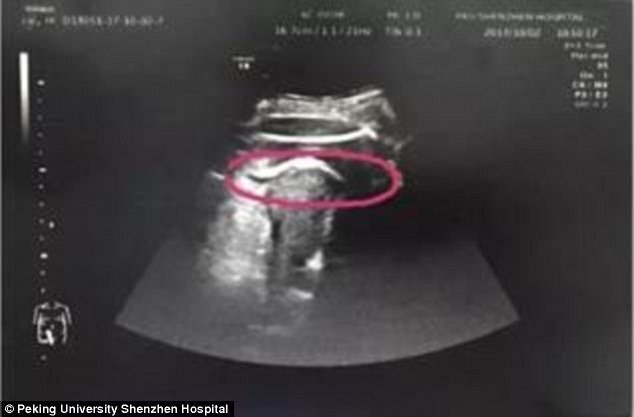

Sản phụ họ Zhang được đưa vào bệnh viện Thâm Quyến cấp cứu trong tình trạng đau bụng dữ dội vì thai nhi đạp thủng tử cung.